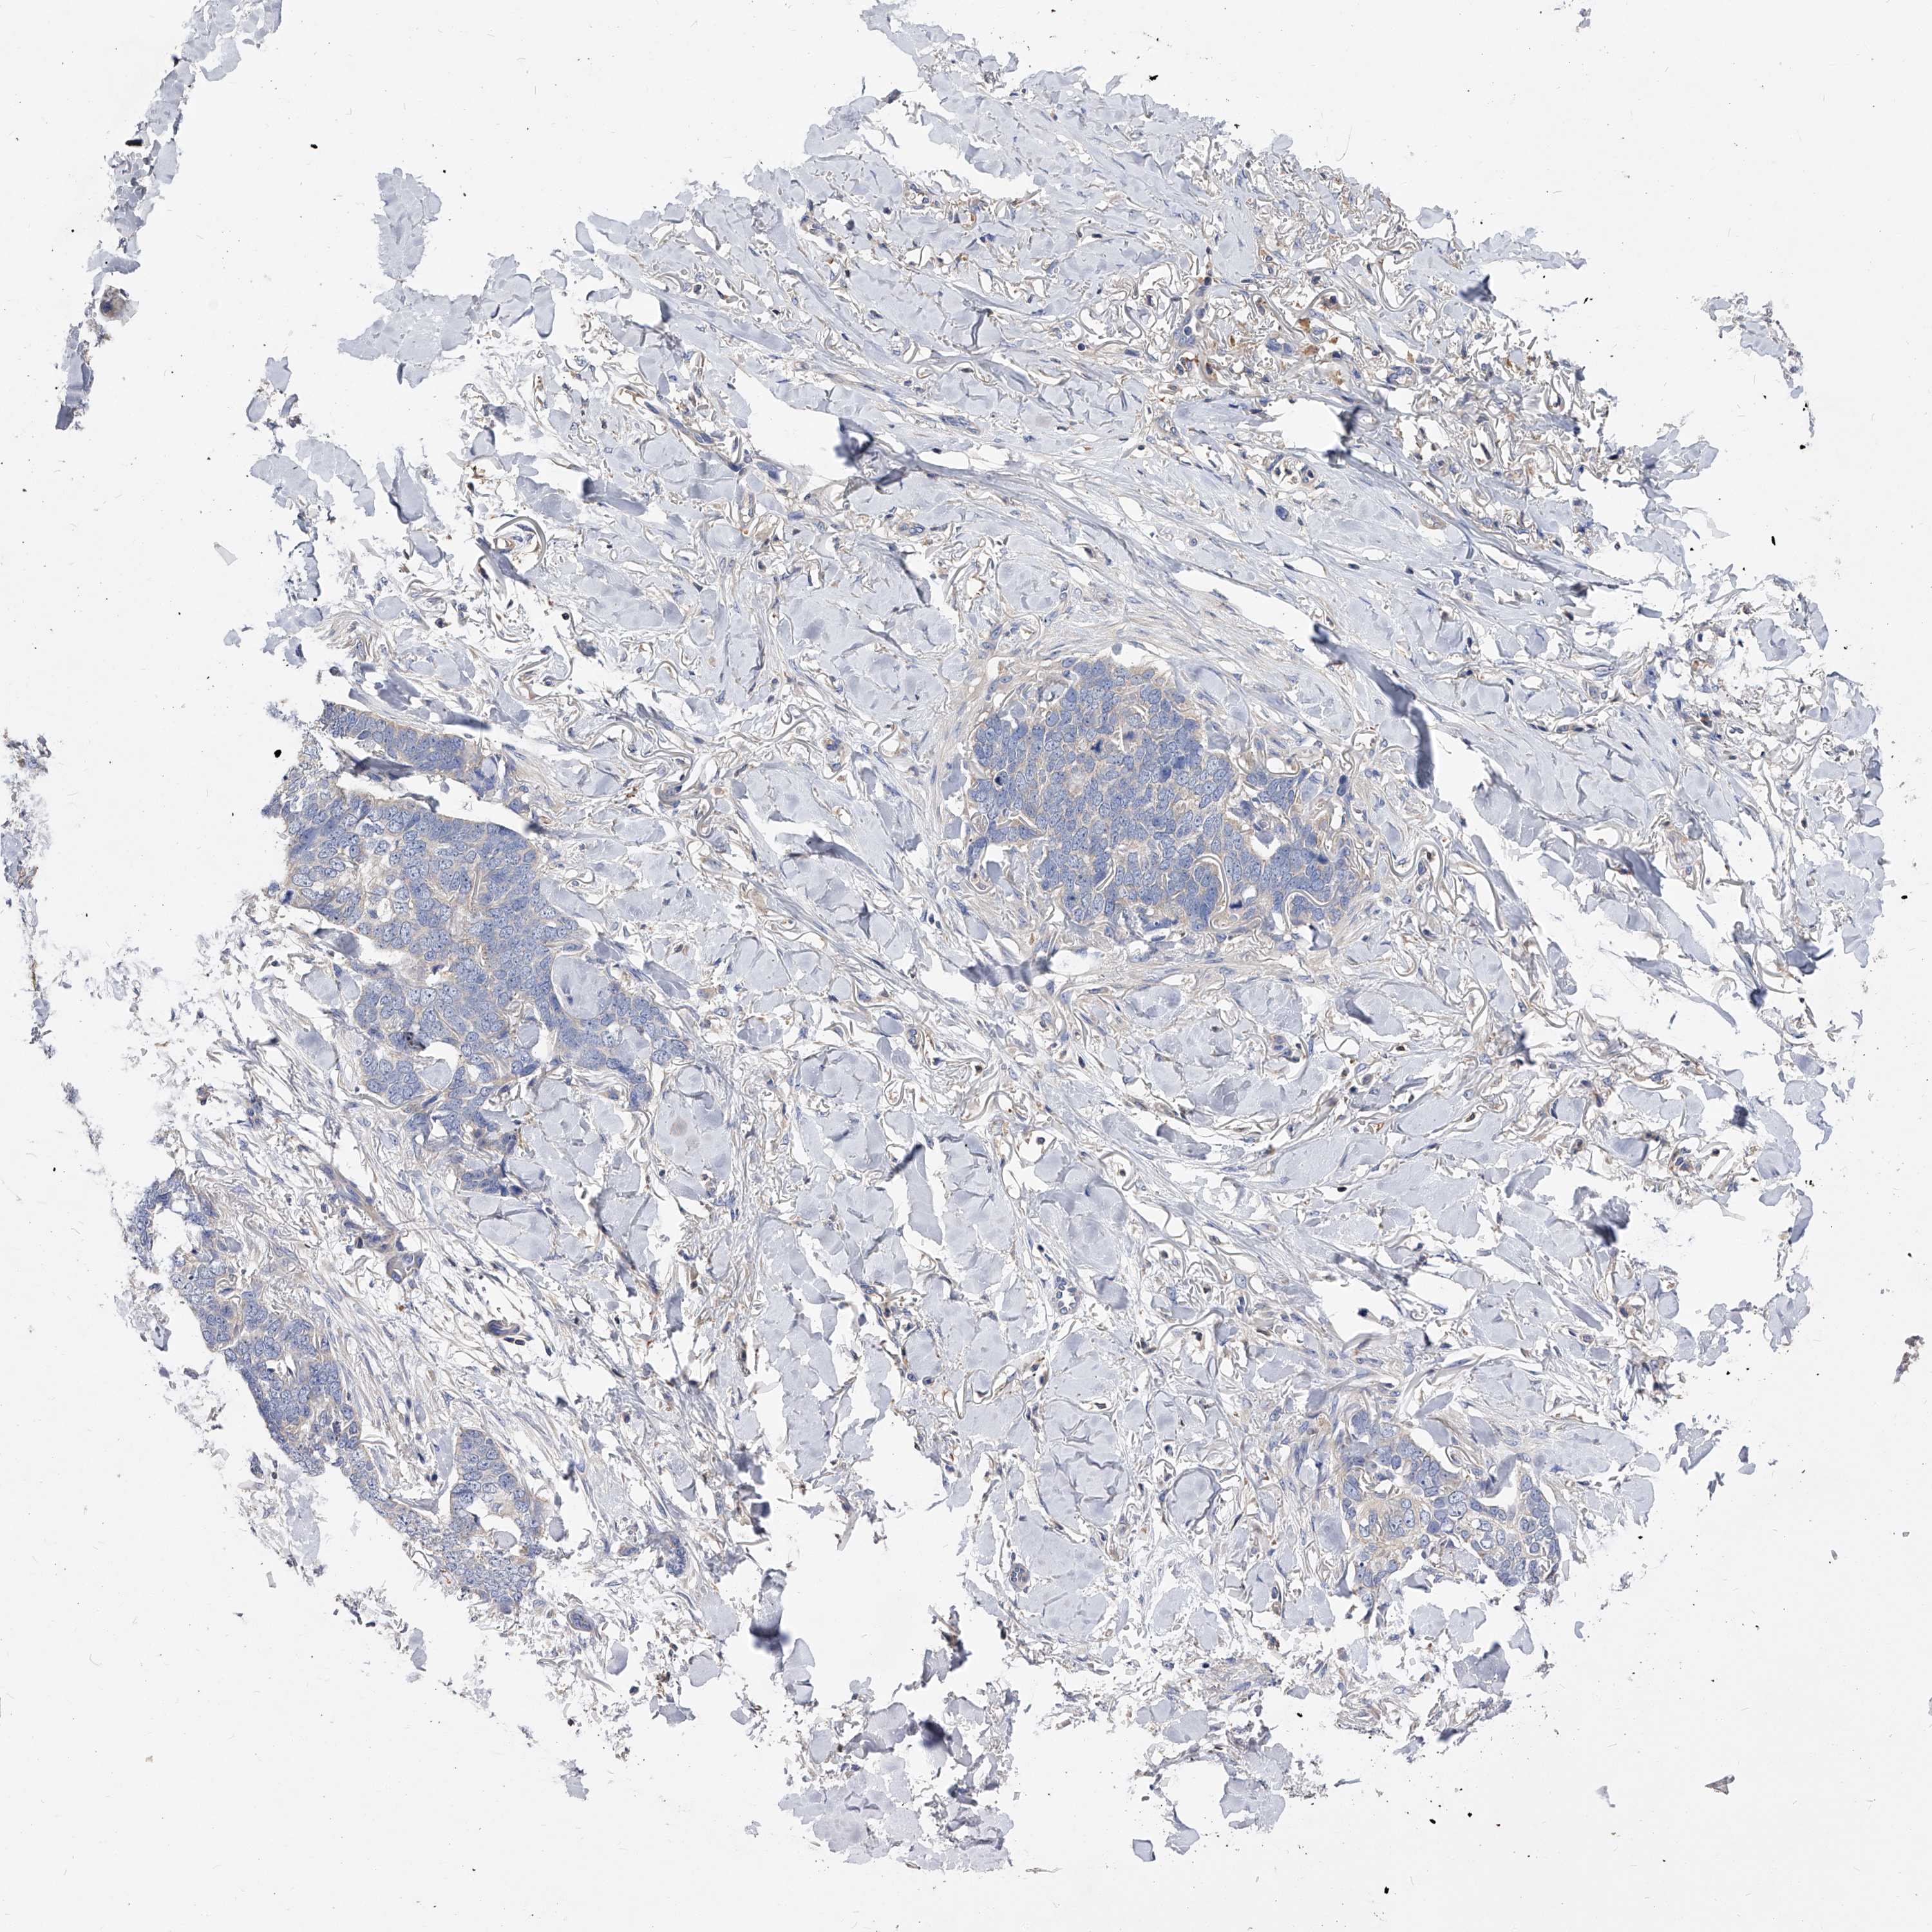

SKIN CANCER - Protein expressioni

A mouse-over function shows sample information and annotation data. Click on an image to view it in a full screen mode. Samples can be filtered based on level of antibody staining by selecting one or several of the following categories: high, medium, low and not detected. The assay and annotation is described here.

Antibody stainingi

Antibody staining in the annotated cell types in the current human tissue is reported as not detected, low, medium, or high, based on conventional immunohistochemistry profiling in selected tissues. This score is based on the combination of the staining intensity and fraction of stained cells.

Each image is clickable and will lead to virtual microscopy that enables deeper exploration of all samples and also displays staining intensity scores, fraction scores and subcellular localization as well as patient and tissue information for each sample.

Antibody HPA029700

Antibody HPA029701

Antibody HPA029702

Antibody HPA029703

Squamous cell carcinoma, NOS